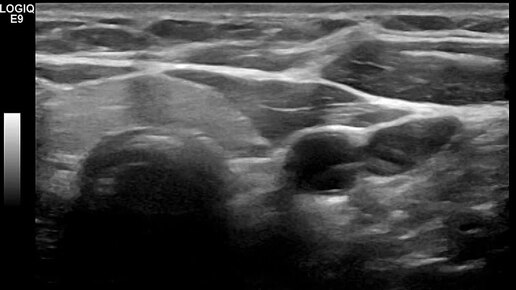

Видео к статье "Аплазия доли щитовидной железы"Адрес: https://dzen.ru/a/aBhLHPV5_mqxaPN7

Ультразвуковые находки от врача УЗД Зорина Я.П.